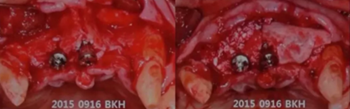

這位患者是2014年來(lái)到我們醫(yī)院

從CT上我們可以看到#14,15,17的牙槽骨被牙齒長(zhǎng)期的牙周炎破壞的非常嚴(yán)重,但是因?yàn)楫?dāng)時(shí)患者不想拔牙,所以暫時(shí)保留下來(lái)。

但是1年之后,因?yàn)榛颊邔?shí)在無(wú)法繼續(xù)使用這些牙齒

所以到我們醫(yī)院進(jìn)行了拔牙

9周后,我們發(fā)現(xiàn)黏膜組織愈合的非常好

11周翻開(kāi)黏膜,我們發(fā)現(xiàn)形成的骨已經(jīng)完全滿足我們種植的需要

我們正常進(jìn)行種植,并在縫隙處放置骨粉。